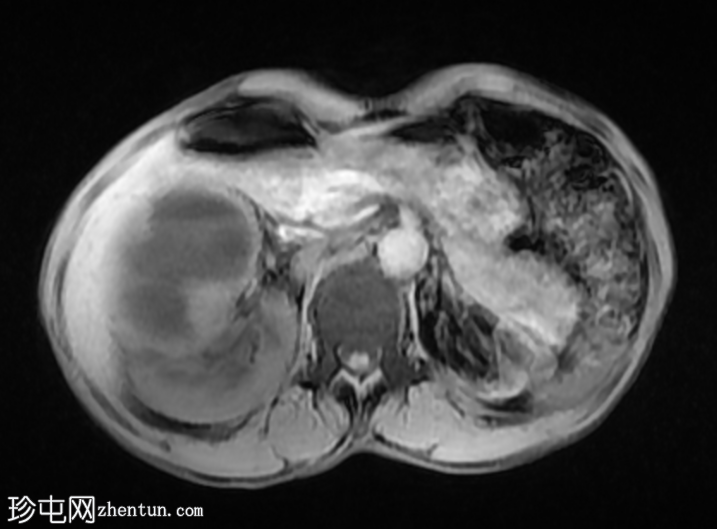

MRI

轴位

STIR序列

T2加权像

再次观察到上述肾前部外生性病变,其实性成分在T1加权像上呈等高信号,在T2加权像上呈低信号,伴有碎片扩散受限和低ADC值(化脓性物质)。囊性成分内部可见液-碎片/脓液界面。可见内部低信号结石。可见肾周模糊影。该病变压迫并可能侵犯右肾盂,导致中度肾积水。

病灶不规则的低信号,以及液-液界面伴有碎屑(可能为化脓性物质)扩散受限和肾周模糊,再次高度提示炎症性病变(黄色肉芽肿性肾盂肾炎,XGP),而非可能性较小的肿瘤。